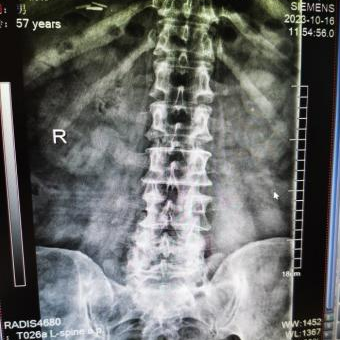

12月17日,贵州航天医院第88次晨读会由我院骨一科主任、副主任医师陈明勇作学术交流,他以“肱骨近端骨折并肩关节脱位的手术治疗”为题,全面讲解了该损伤的手术策略、术中血供保护理念及内侧支撑重建技术等内容,并通过多个典型病例图文资料分享了从损伤机制分析、手术步骤实施到术后随访评估的完整过程与关键细节,为临床处理此类复杂骨折提供了较为全面的技术参考,有助于在手术规划中结合个体情况开展针对性治疗。 贵州航天医院 骨科专家简介 陈明勇 骨一科主任,副主任医师 临床擅长:从事创伤骨科工作约20年,对骨缺损、骨不连、骨肿瘤、肢体畸形等的肢体矫形重建及功能重建,慢性化脓性骨髓炎的根治治疗、糖尿病足的保肢治疗、快速康复理念(ERAS)下的老年骨折的诊治,四肢复杂骨折的诊治,四肢骨折等微创手术治疗具有丰富的临床经验。 2004年毕业于遵义医学院临床专业,曾在中国人民解放军总医院、广西医科大学第一附属医院、上海第六人民医院骨科进修。中国中西医结合学会骨伤科专业委员会横向骨搬移治疗糖尿病足及微血管网再生学组首届委员,遵义市医学会创伤分会常务委员。 瞿 晖 骨科党支部书记,骨二科主任,副主任医师 临床擅长:对骨科的常见病、关节外科、脊柱外科及运动医学疾病的诊治具有丰富的临床经验,熟练掌握骨科手术操作技术。 毕业于遵义医学院临床医学系,2005年前往广州中山大学第一附院骨显微医学部进修学习,2011年前往成都华西医院进修学习,并多次在省内外学习骨科相关知识,是中华医学会骨科分会会员。 赵小锋 中共党员,骨二科副主任,副主任医师 临床擅长:从事骨科临床工作11年,对骨科常见病、多发病诊疗有较为丰富的临床经验,擅长脊柱相关疾病诊断及治疗,尤其是颈、腰、腿疼痛疾病诊断及治疗,擅长胸腰椎骨折微创经皮穿刺内固定术、经皮穿刺椎体成形术、经皮穿刺脊柱内镜下腰椎间盘摘除术、单纯开创腰椎间盘摘除术、腰椎滑脱复位椎间植骨椎融合内固定术、腰椎管狭窄减压融合内固定术及人工髋、膝关节置换术等。 2012年毕业于遵义医学院外科学专业硕士研究生,2019年参加“遵义市115医学人才精英计划”于上海交通大学第一附属医院培训学习,2023年于北京大学第三人民医院脊柱外科进修学习,曾获得遵义市优秀医师荣誉称号。 遵义市手外科第一届委员,遵义市医学会创伤分会第一届委员,遵义市医学会创伤分会第二届委员,贵州省康复医学会第三届脊柱脊髓专业会委员,遵义市医学会烧伤与整形外科学分会委员,发表论文5篇,其中国家级核心期刊1篇,SCI论文1篇,主持市级课题1项并结题,参与市级课题2项。 赵兴东 骨科主任医师 临床擅长:擅长骨科的常见病及各种创伤、四肢骨折创伤修复、骨感染、手足疾病的诊治和手足体表畸形的矫形整复,熟练掌握骨科四肢骨病及创伤的手术操作技术,尤其在四肢关节复杂性损伤、手足外伤、组织缺损创面、难治创面的皮瓣修复方面及平足、高弓足矫形方面及四肢慢性疼痛诊治、康复方面具有丰富的临床经验。 硕士研究生,毕业于遵义医学院临床外科系,2015年前往山东省立医院手足外科进修学习;遵义市医学分会创伤分会第一、二届委员,遵义市手外科医学会第二委届员会常务委员;在省级及省级以上期刊发表文章9篇,参编著作2部,参与主持并完成市级课题1项,参与市级课题2项、省级课题1项。 张艳金 中共党员,骨科副主任医师 临床擅长:从事骨外科工作16年,对复合伤、多发伤的救治、四肢骨干骨折、关节周围骨折、骨肿瘤、骨髓炎等诊治具有丰富的临床经验。 中共党员,硕士研究生,2006年本科毕业于山西医科大学第二临床医学院,2011年研究生毕业于北京军区总医院;在“老年COPD患者合并髋部骨折的诊治”国际合作课题组研究两年,在老年髋部骨折的诊治方面具有丰富的经验,并发表论文6篇;主持遵义市级课题1项,承担遵义医科大学的临床教学工作,获得遵义医科大学优秀带教老师荣誉。编撰有《骨科疾病诊疗精粹》一书,开展2项新技术,编撰地方规范《务川自治县创伤骨科常见疾病诊疗规范》一书。 张俊凯 骨科副主任医师 临床擅长:从事骨科临床工作28年,对创伤骨折、骨感染、骨缺损、骨不连等外科诊治,四肢骨折的微创手术治疗,四肢复杂骨折(如关节内粉碎性骨折、多发骨折等)的损伤控制及手术治疗等具有丰富的临床经验。 1995年毕业于遵义医学院临床专业,2009年前往复旦大学附属医院骨科进修1年。 卢懿明 中共党员,骨科副主任医师 临床擅长:从事骨科工作18年,对创伤骨折、四肢骨折的微创手术治疗、四肢复杂骨折(如关节内粉碎性骨折、多发骨折等)的损伤控制及手术治疗,尤其是髋部骨折的PFNA等微创技术,踝关节骨折、膝关节周围骨折的Mipo微创技术等具有丰富的临床经验,开展了4项新技术,发明6项新型专利技术。 2005年毕业于遵义医学院临床专业,2017年,前往南方医科大学第三附属医院骨科进修半年,回院后运用Mipo技术对骨干骨折及干骺端骨折的治疗技术,同时积极开展骨盆骨折、髋臼骨折腹直肌外侧切口的应用;发表了多篇专业论文,经常参与省内外学术交流会授课,获得医院荣誉称号多个。 邬夏荣 骨科副主任医师 临床擅长:从事骨科工作16年,对四肢复杂骨折、骨肿瘤的诊治,尤其是足踝创伤、慢性踝关节损伤、平足症等诊疗具有丰富的临床经验。 2006年毕业于遵义医科大学临床医学专业,曾在陆军军医大学西南医院进修学习,发表多篇骨科学术论文。 余德怀 中共党员,骨科副主任医师 临床擅长:从事骨科工作10余年,对运动医学、骨关节、脊柱外科常见病、多发病的诊治具有丰富的临床经验。 硕士研究生,2011年毕业于遵义医学院临床医学专业,曾前往遵义医科大学附属医院运动医学专业进修学习;是贵州省医学会运动医学分会青年委员,西部关节镜联盟委员;发表多篇骨科学术论文。 冯 乾 骨科副主任医师 临床擅长:从事骨科工作近20年,熟练掌握骨科多发病及常见病的诊治,尤其对脊柱退变性疾病的诊断及治疗具有丰富的临床经验,主要研究脊柱微创相关治疗方式,能熟练开展椎间孔镜及UBE。 曾前往北京大学第三医院进修学习疼痛及椎间孔镜、首都医科大学友谊医院专业进修脊柱内镜;是贵州省康复医学会第三届脊柱脊髓专业委员会委员;发明专利3项、发表脊柱外科专业论文多篇。 贵州航天医院骨科简介 基本情况 贵州航天医院(原3417医院)骨科组建于1968年,前身是以创伤和断肢(断指)再植闻名于世的上海市第六人民医院骨科,中国断肢(断指)再植的奠基者、中科院院士陈仲伟等专家莅临科室指导医疗和教学,并在70年代开展了贵州省首例断肢(断指)再植手术。组建50余年来,诊治患者已逾百万,挽救了无数的伤病员,成为了保障遵义地区人民群众健康的重要支撑。 经过几代人的不懈努力,今天的骨科,已由创伤骨科发展至骨病、骨肿瘤、骨结核等领域,现有脊柱外科、关节外科、四肢创伤、手足外科四个亚专科,成为了集医疗、教学、科研于一体的综合学科,是贵州省临床重点专科、遵义市临床重点专科、遵义市骨科临床医学中心、遵义市基层骨科专科联盟理事长单位。 科室目前开放床位110张,共有医护人员50余人,副高级以上专家18人,硕士研究生15人。拥有一流骨科医疗设备多台,每年不定期选派优秀技术骨干到全国各大知名医学院校进修、学习、参观、交流,并邀请国内、国外知名专家教授来院进行交流、指导,通过不断引进国内外先进的诊疗技术,科室医疗技术水平稳步提升,为广大人民群众提供了优质的医疗服务。 专科特色 骨一科 (一)骨缺损、骨不连的肢体与功能重建 胫骨横向骨搬移技术治疗糖尿病足: (二)慢性骨髓炎的根治治疗 (三)肢体缺血性疾病如糖尿病足、脉管炎的保肢治疗 (四)皮瓣修复 (五)复杂创伤的治疗 (六)老年髋部骨折及小儿骨折快速手术 老年髋部骨折: 骨二科 (一)胸腰椎骨折微创经皮椎弓根螺钉固定术 (二)老年性骨质疏松性患者腰椎滑脱脊柱内固定术(骨水泥螺钉) (三)V形双通道脊柱内镜技术(VBE)腰椎融合术治疗腰椎退行性疾病 (四)老年性骨质疏松性骨折(PVP/PKP)术 (五)人工髋关节置换术 (六)双侧股骨头坏死人工全髋关节置换 (七)右侧全髋置换术后假体周围骨折翻修 (八)人工膝关节置换术 (九)人工膝关节假体松动翻修 (十)关节镜技术 传统手术切口 关节镜技术切口 诊疗范围 骨一科 1.四肢创伤、矫形。 2.手、足踝外科。 骨二科 end